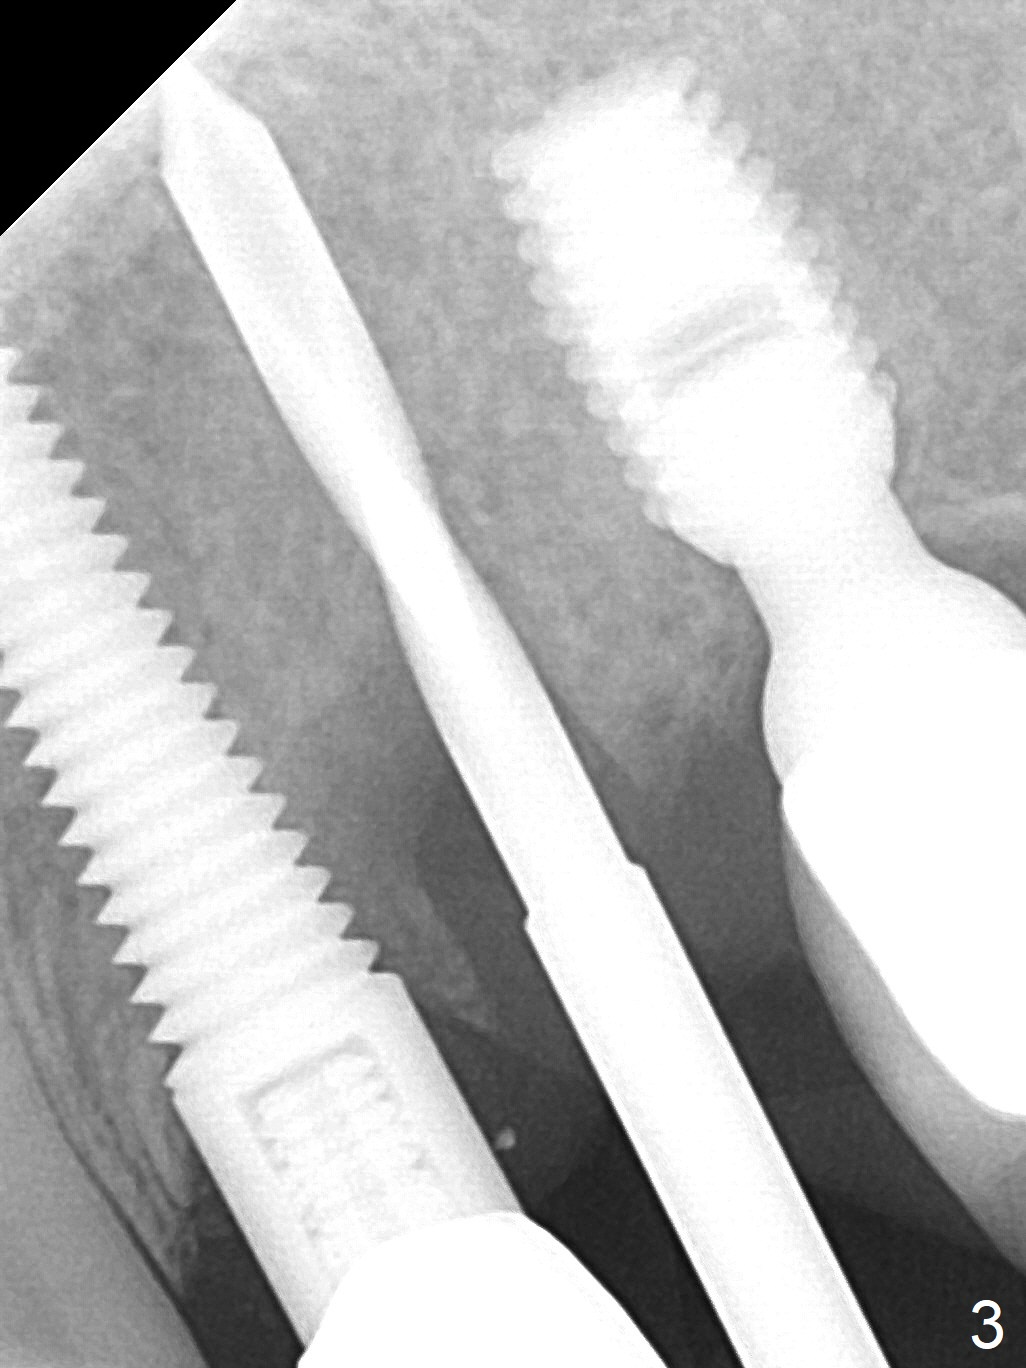

The root of the tooth #13 has an oblique fracture as related to a prefabricated post after 9 years of service (Fig.1). The trajectory of the initial osteotomy (Fig.2) is corrected with Lindamann bur and reuse of 2 mm drill (Fig.3). A 4x20 mm tissue-level implant is placed with > 60 Ncm, followed by tightening a 3.5x5 mm abutment (Fig.4,5); the mesiobuccal defect being filled with Vera Graft (Fig.4 *). An immediate provisional is fabricated. It appears that the implant should have been placed deeper (Fig.6: 5 months postop).